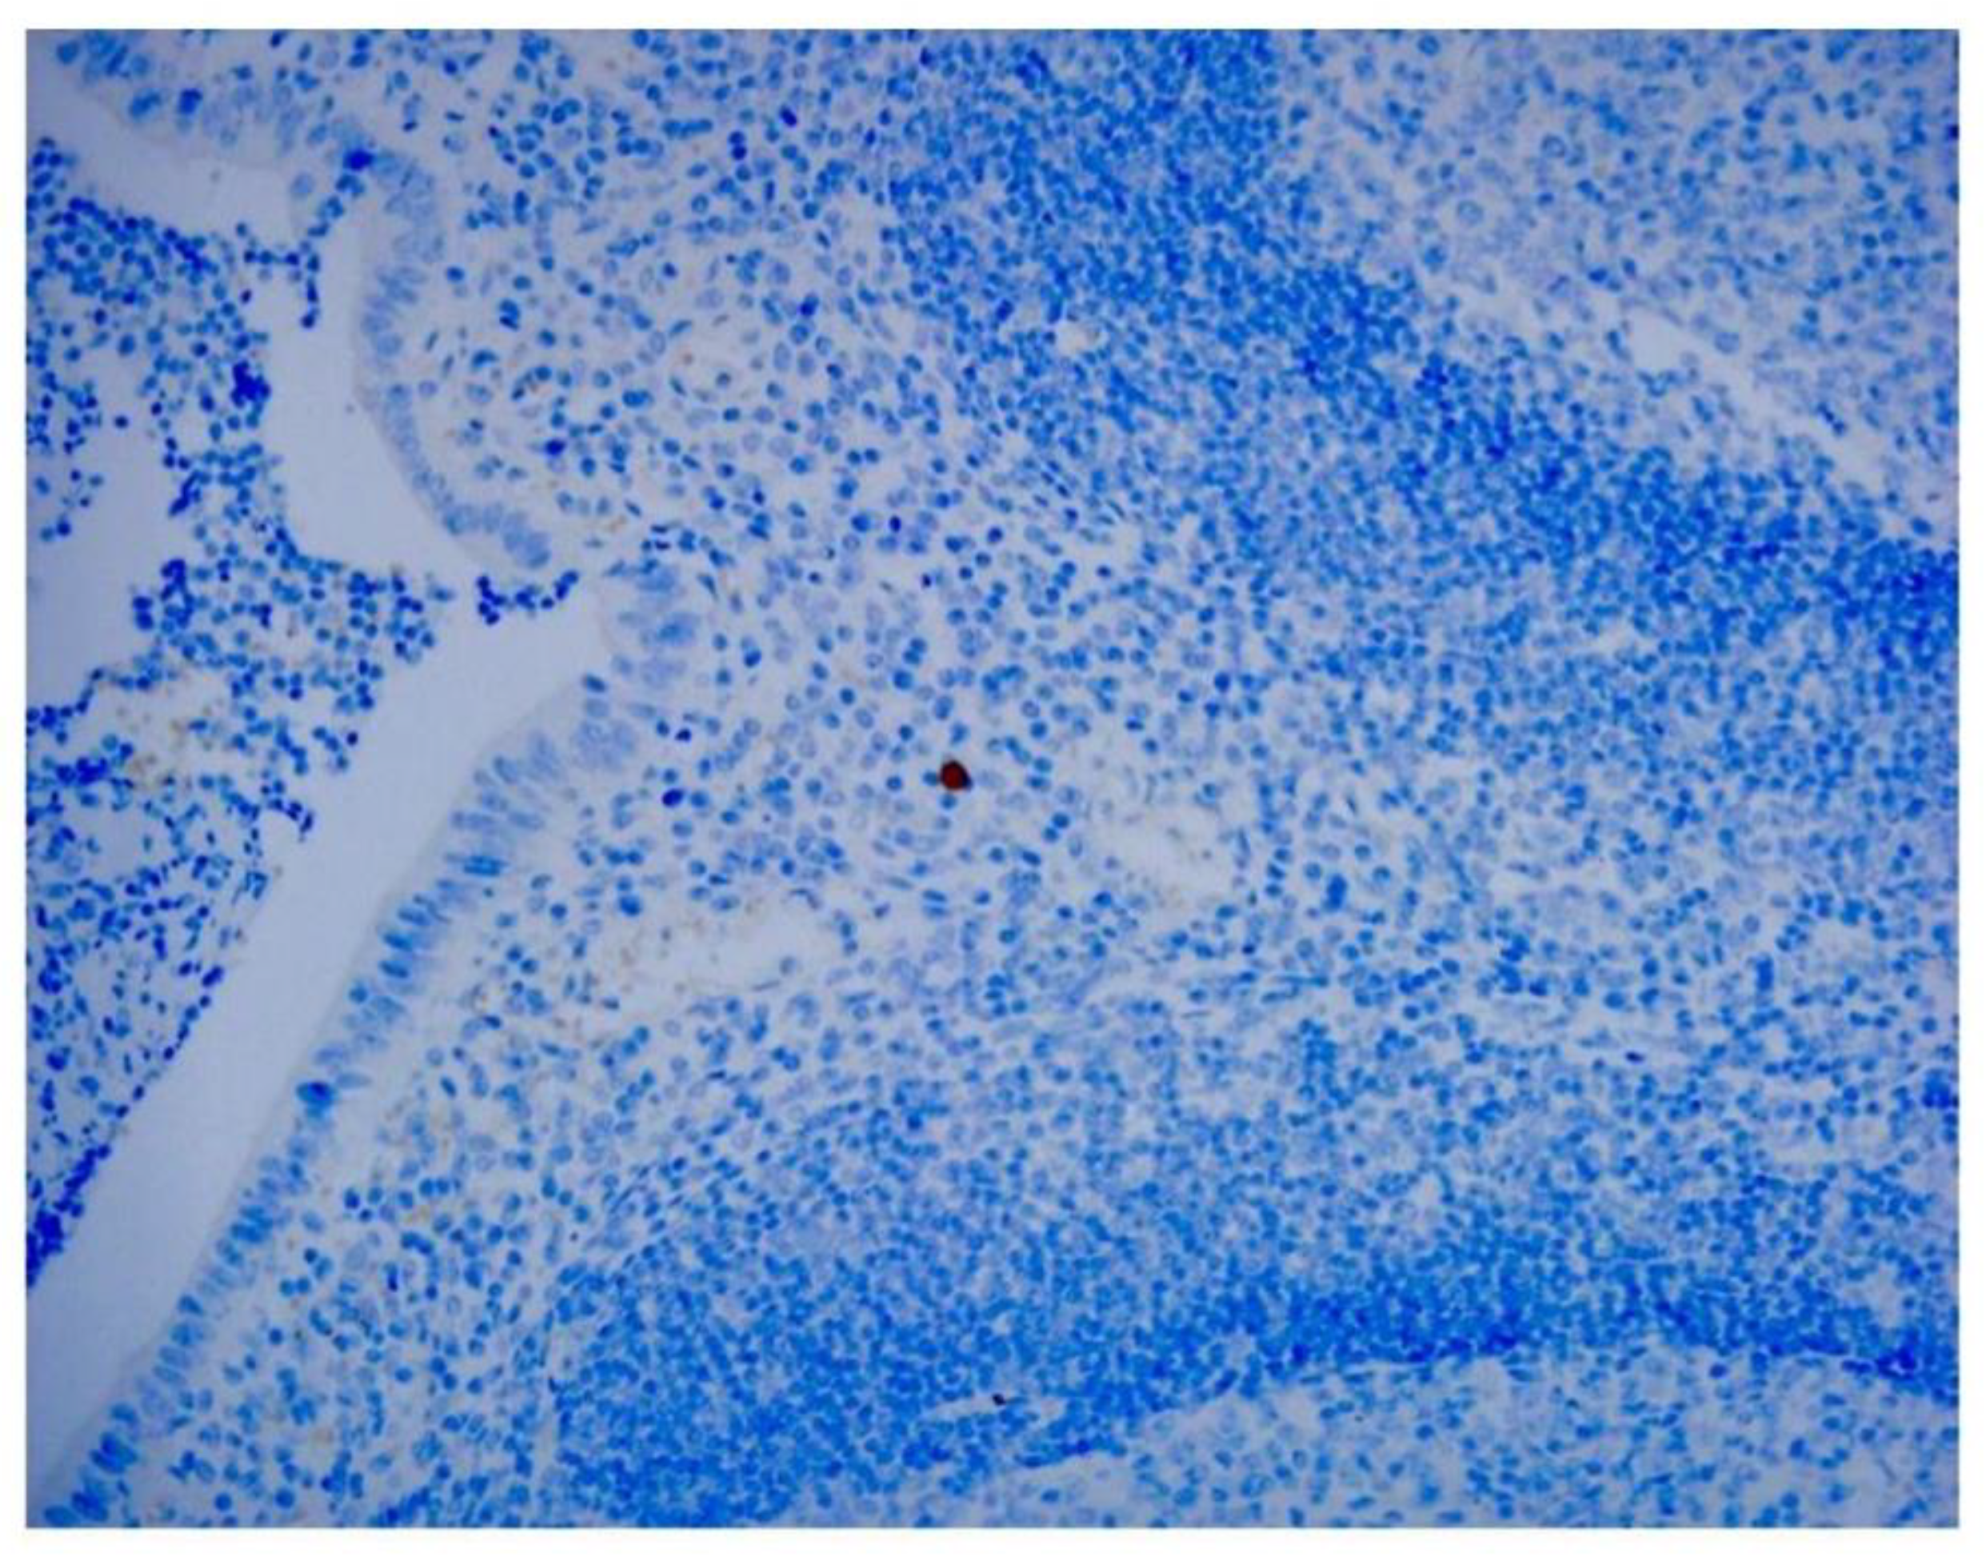

Among the 8 specimens, 3 were positive for adenovirus by IHC (37.5%), and 4 were positive by PCR (50%). None of the control subjects was positive in IHC (Figure 4) and PCR analyses. We combined IHC and PCR results and showed that the adenovirus detected in this study is serotype C (Figure 5). Our pathological evidence directly confirms the relationship between adenovirus infection and intussusception. IHC and PCR analyses confirmed evidence of adenovirus infection in patients with intussusception. Compared with the control group, the P-value for IHC was greater than 0.05, showing no statistical difference, while the P-value for PCR was less than 0.05, showing a statistical difference (Table 1 and Table 2). For diagnosing adenovirus in intussusception, PCR is as useful and reliable as IHC and is more sensitive.

Figure 4. An immunohistochemical assay using anti-adenovirus antibody reveals that a patient in the control group has negative results (original magnification ×40).